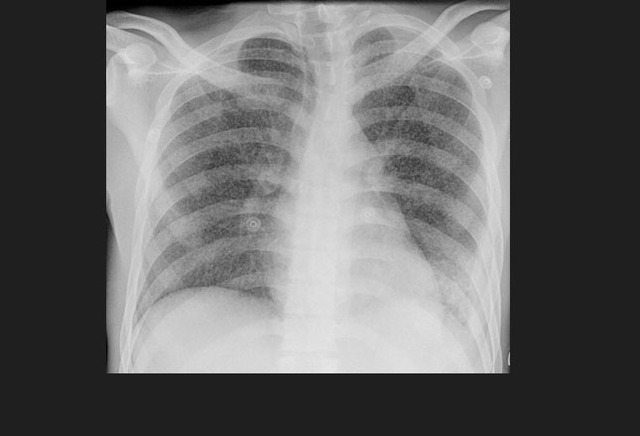

图1. 一位进展性肺结核患者双侧胸腔积液(左侧较右侧严重)。